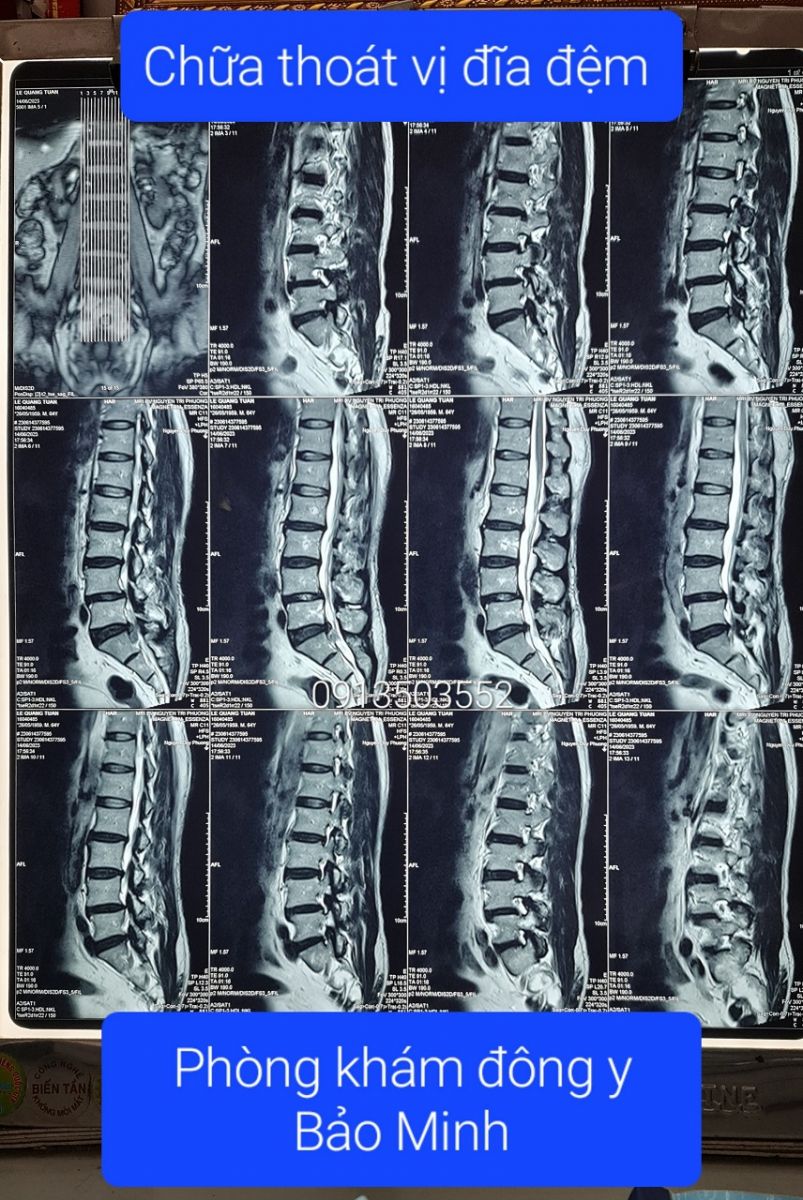

Chữa thoát vị đĩa đệm chèn ép rễ thần kinh cho chú Hùng ở Bình Dương.

Lương y Nguyễn Văn Minh - Phòng khám Đông y Bảo Minh chỉ chia sẻ ý kiến và kết quả MRI khi được sự đồng ý từ quý khách, sau này quý khách nào không muốn xuất hiện ở đây nữa, chúng tôi sẽ gỡ bài đăng xuống. Xin trân trọng cảm ơn quý khách đã tin tưởng vào uy tín của phòng khám.❮ đọc tiếp ❯ -

Thoát vị đĩa đệm dạng trung tâm, có rách vòng xơ.

Thoát vị đĩa đệm dạng trung tâm tầng L4-L5, có rách vòng xơ, có mảnh rời di trú xuống dưới ở ngách bên phải, ép mặt trước bao màng cứng, chèn rễ L5 phải. Thoái hóa cột sống thắt lưng.❮ đọc tiếp ❯ -